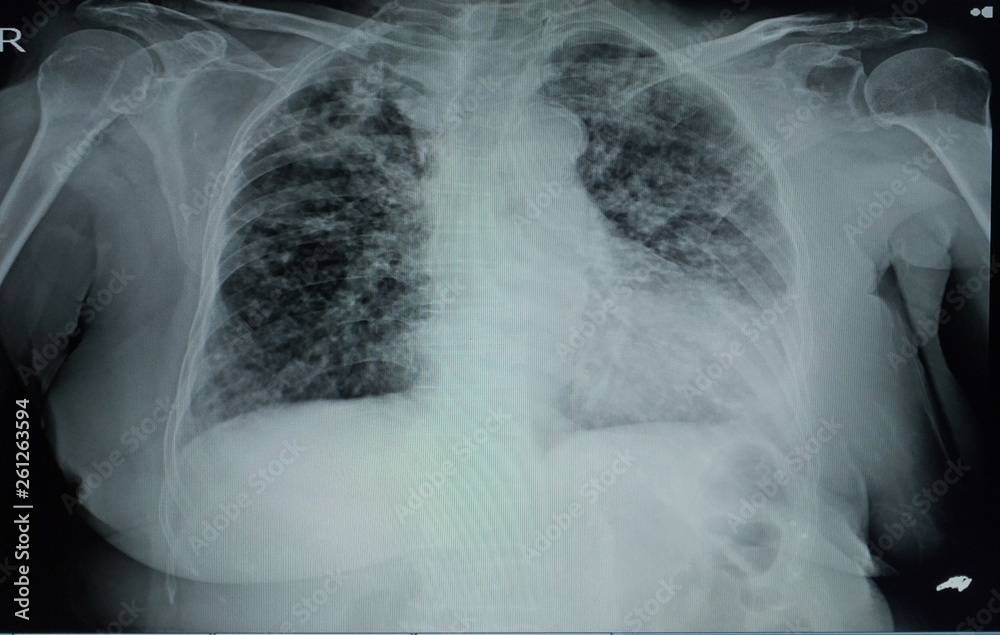

From www.researchgate.net

Lung bases demonstrate multiple nodular densities from the midlung What Is Lung Nodular Density  It shows up as a white spot on a ct. Lung nodules are very common and are estimated to occur in. Nodules are areas that are denser than normal lung tissue and usually don't cause symptoms. Commonly called a “spot on the lung” or a “shadow,” a nodule is a round area that is more dense than normal lung tissue.. What Is Lung Nodular Density.